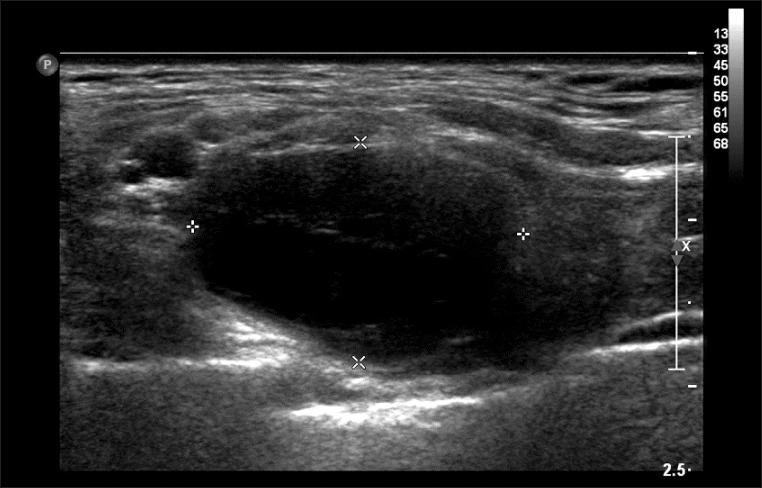

Schwannomas are benign, usually slow-growing tumors that originate from Schwann cells surrounding peripheral, cranial, or autonomic nerves. The most common form of these tumors is acoustic neuroma. Schwannomas of the brachial plexus are quite rare, and symptomatic schwannomas of the brachial plexus are even rarer. A 47-year-old woman presented with a 1-year history of dysesthesia, neuropathic pain, and mild weakness of the right upper limb. Results of physical examination and electrodiagnostic studies supported a diagnosis as thoracic outlet syndrome. Conservative treatment did not relieve her symptoms. After 9 months, a soft mass was found at the upper margin of the right clavicle. Magnetic resonance imaging showed a 3.0×1.8×1.7 cm ovoid mass between the inferior trunk and the anterior division of the brachial plexus. Surgical mass excision and biopsy were performed. Pathological findings revealed the presence of schwannoma. After schwannoma removal, the right hand weakness did not progress any further and neuropathic pain gradually reduced. However, dysesthesia at the right C8 and T1 dermatome did not improve.

施万细胞瘤是良性肿瘤,通常生长缓慢,起源于周围神经、颅神经或自主神经周围的施万细胞。这些肿瘤最常见的形式是听神经瘤。臂丛神经施万细胞瘤相当罕见,有症状的臂丛神经施万细胞瘤更为罕见。一名47岁女性,有1年的感觉异常、神经性疼痛和右上肢轻度无力病史。体格检查和电诊断研究结果支持胸廓出口综合征的诊断。保守治疗未能缓解她的症状。9个月后,在右锁骨上缘发现一个柔软肿块。磁共振成像显示在臂丛神经下干和前支之间有一个3.0×1.8×1.7 cm的椭圆形肿块。进行了肿块切除和活检。病理结果显示为施万细胞瘤。切除施万细胞瘤后,右手无力未进一步发展,神经性疼痛逐渐减轻。然而,右侧C8和T1皮节的感觉异常没有改善。